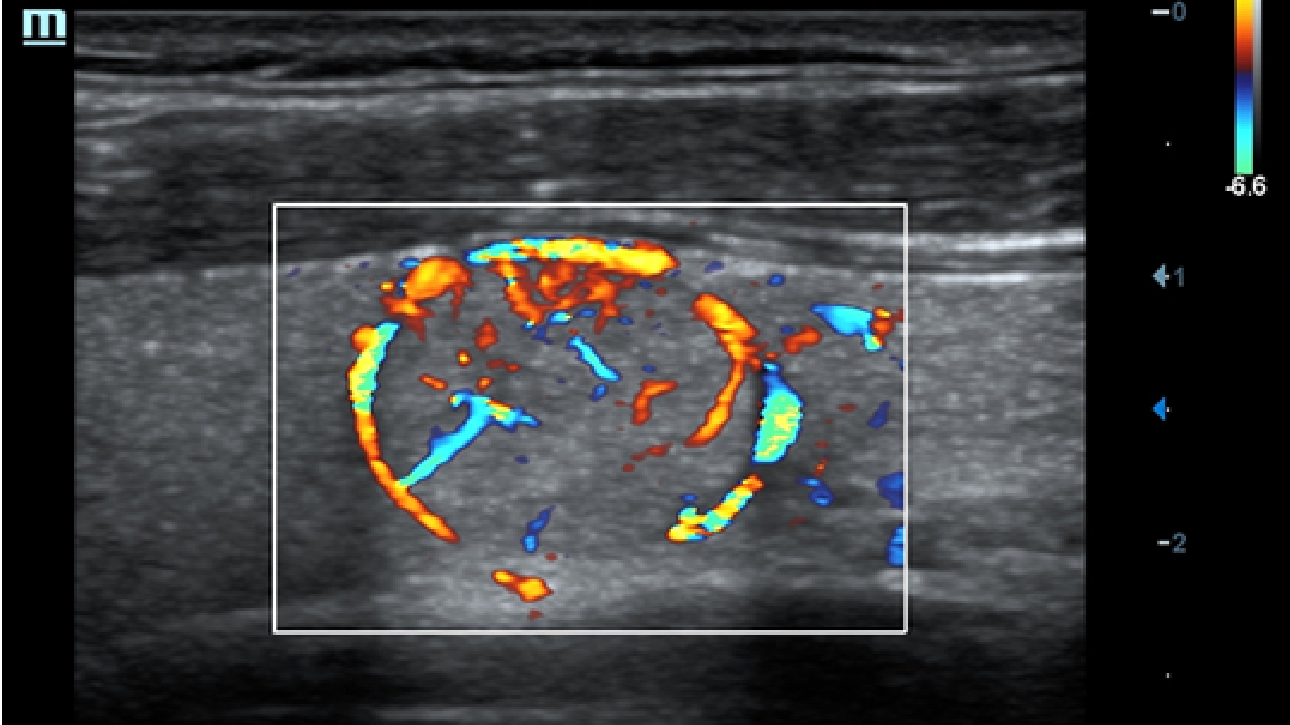

Obrazy kliniczne